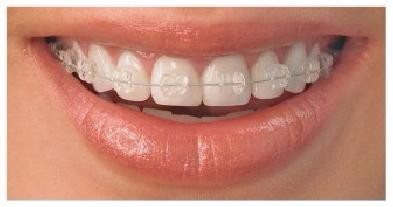

用老话讲就是“箍牙”!传统认知里的矫正就是用一嘴钢丝,慢慢牙齿就齐了。其实牙齿矫正是通过各种矫治器对牙齿进行移动,从而对牙齿位置进行改建,甚至会极大的改善面部形象和面部骨骼和肌肉的协调性。